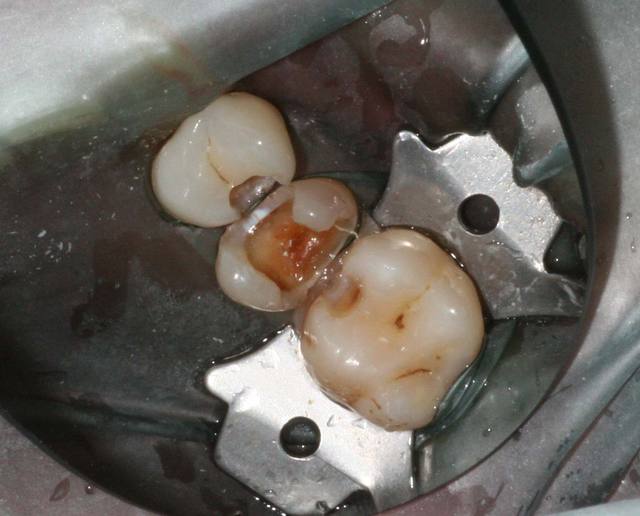

puisque c'est calme on va poser des questins cons.

alors que feriez vous pour ce patient qui a "perdu un plomb", il n'a pas de sensibilité et la 15 est vivante.

C img 1979 vvqafb - Eugenol

Save0001 z8k0bx - Eugenol